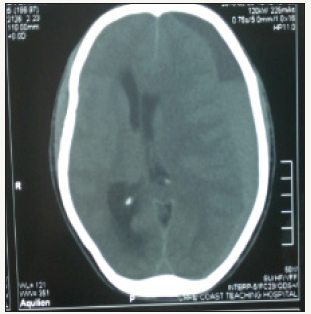

A non-contrast head computed tomography scan showed a left front-parietal chronic subdural hematoma with marked midline shift as depicted in (Figure 1 & 2). A clinical diagnosis of Kernohan- Woltman notch phenomenon was made. Emergency burr hole drainage of the chronic subdural hematoma using a double burr hole technique was done. Patient regained consciousness twelve hours post-operatively but was noticed to have an ipsilateral left hemiparesis and a persistent left eye mydriasis. The patient was discharged home on post-operative day 5 after full recovery with no residual neurological deficits. The patient on follow up visit three (3) weeks after surgery was found to be doing well with no residual neurological deficit.

figure 1:A left frontoparietal chronic subdural hematoma with a sub-acute component showing significant midline shift.

figure 2:Axial CT scan at a different level with left frontoparietal chronic subdural hematoma showing a midline shift.